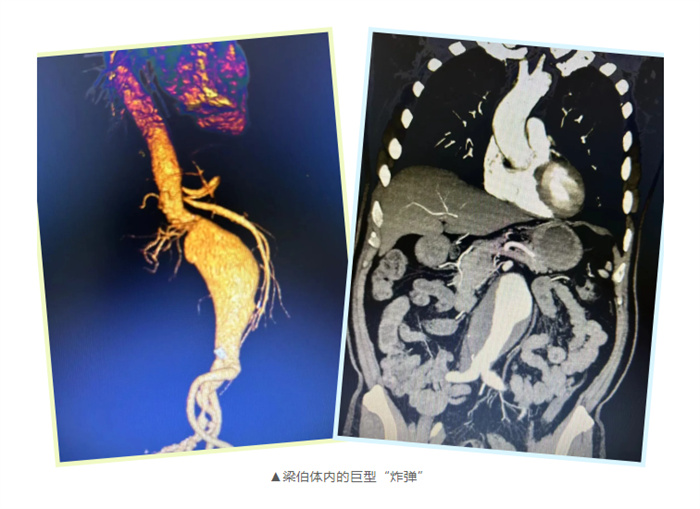

腹主動(dòng)脈瘤俗稱“人體炸彈”,一旦破裂,體內(nèi)會(huì)短時(shí)間大量出血導(dǎo)致患者休克甚至死亡。有研究顯示,腹主動(dòng)脈瘤破裂后死亡率高達(dá)90%。然而,大多的腹主動(dòng)脈瘤并沒有特殊的臨床表現(xiàn),容易被忽略。

近日,75歲的梁伯在一次CT檢查時(shí)發(fā)現(xiàn)自己得了腹主動(dòng)脈瘤。自從得知自己的病情后,他臉上時(shí)?;\罩著一層陰霾。家人看在眼里,疼在心里,他們四處打聽,希望能找到更好的治療方法。最終,他們來(lái)到了南方醫(yī)科大學(xué)順德醫(yī)院就診。

心胸外二科副主任韋高翔仔細(xì)評(píng)估了梁伯的狀況,“該患者除了有腹主動(dòng)脈瘤外,還合并了高血壓;一度房室阻滯;全主動(dòng)脈多發(fā)鈣化斑、附壁血栓及穿透性潰瘍形成;冠心病,三支病變:左主干-左前降支、回旋支等幾乎閉塞?!表f高翔說(shuō)道。